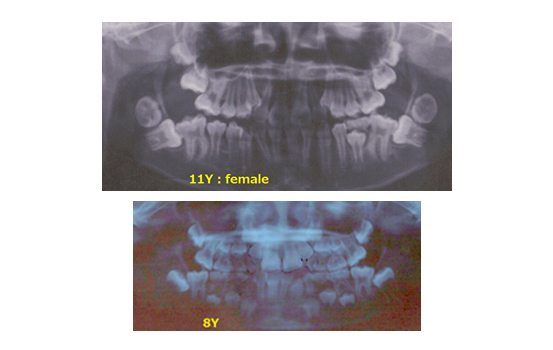

叢生(1期治療)

初診時7歳男の子:治療期間 1 年 10 か月目)( No246―No 2202*2026 年 4 月号)

受け口(反対咬合)

初診時6歳女の子:治療期間3年8か月目( No245―No2161 *2026年3月号)

初診時8歳女の子:主訴 上顎前突

( No244―No1951 *2026年1&2月号)